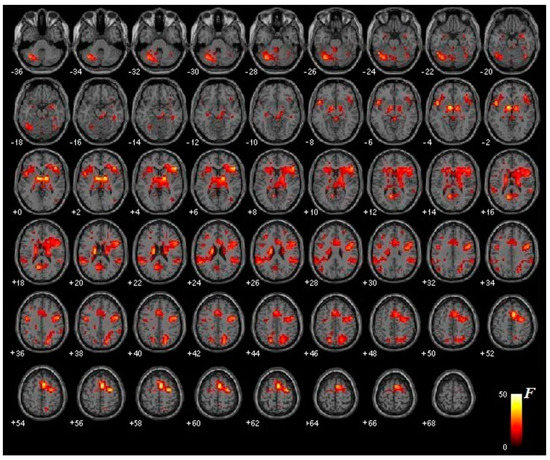

3.2. Functional Brain Activation